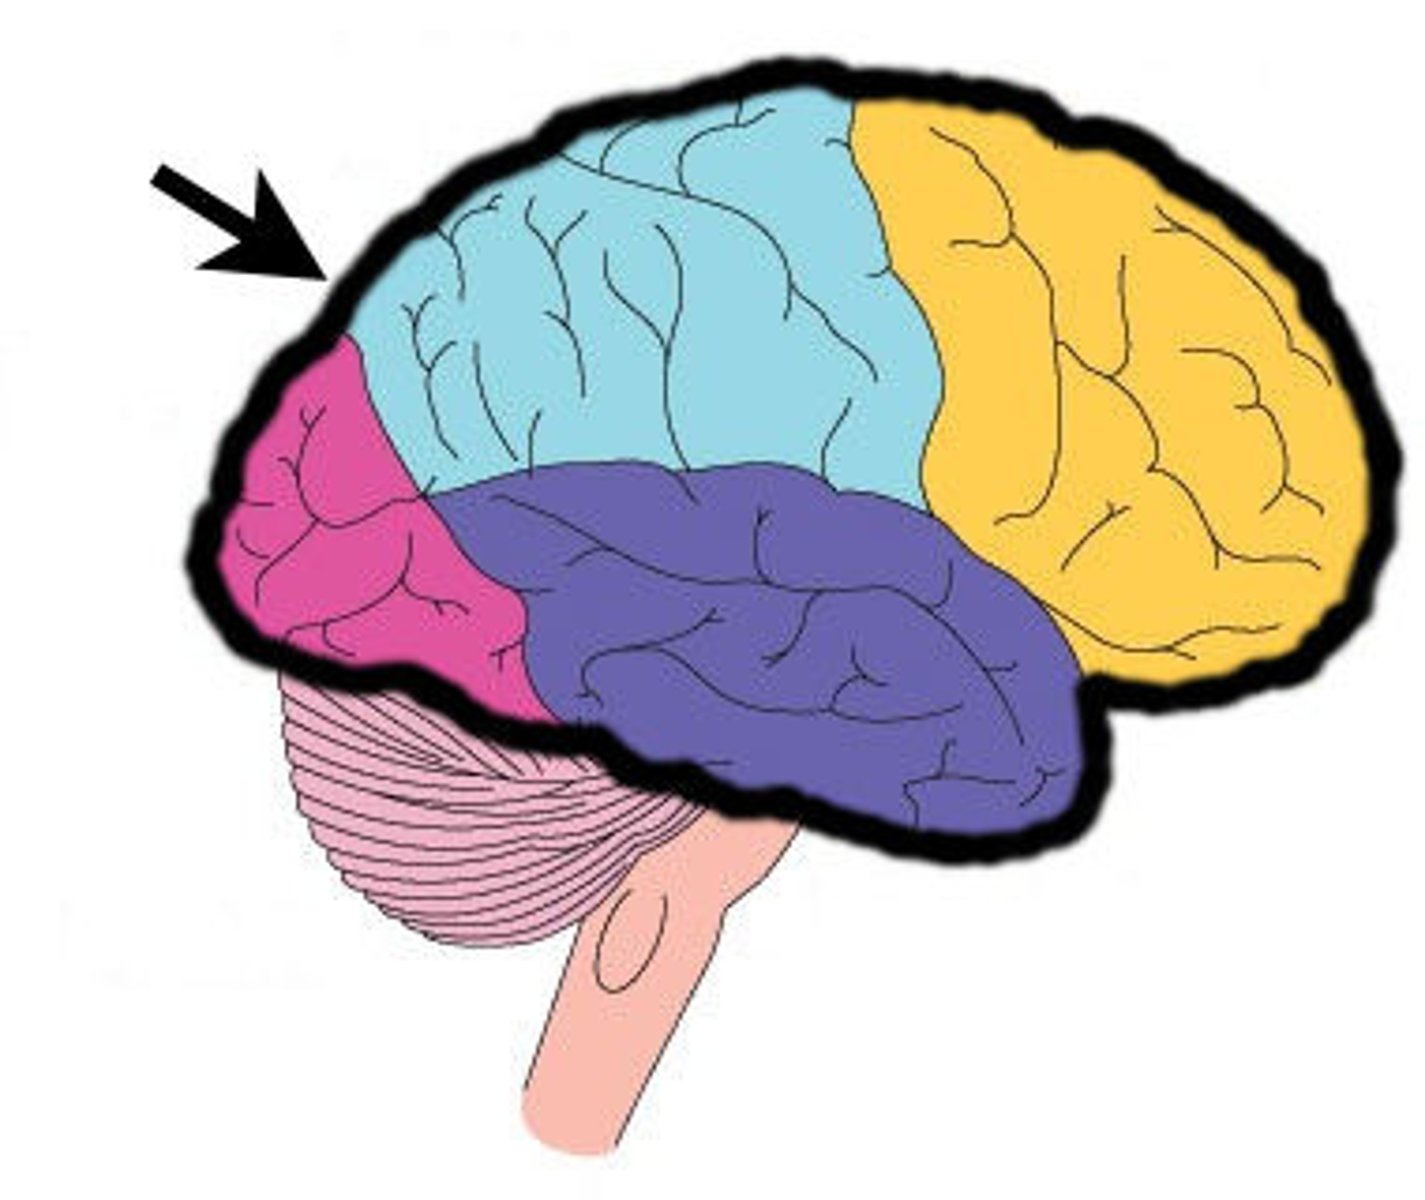

frontal lobe

associated with social cues, personality, planning, movement, emotions, and problem solving - contains primary motor cortex

precentral gyrus

primary motor cortex

parietal lobe

A region of the cerebral cortex whose functions include processing information about touch, contains primary somatosensory cortex

postcentral gyrus

primary somatosensory cortex

occipital lobe

visual center

temporal lobe

language centers, auditory processing, olfactory